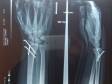

Здравствуйте. В горах сломал запястье. В травм.пункте вставили на место и направили в больницу на фиксацию спицами (операция была на следующий день после перелома). Вопросов несколько: 1. Как на ваш взгляд поставлены спицы? Отлично, хорошо, удовлетворительно, плохо? 2. Прошел месяц с даты перелома, рука постепенно возвращается в работу. Кроме физ.упражнений и минимальных нагрузок, на какую терапию стоит ходить (тепло, ток, магнио), какие витамины/добавки принимать? 3. Когда стоит сделать повторный снимок? Когда доставать спицы? Спасибо.

3) Контрольную рентгенографию можно выполнить сейчас и по ее результатам определяться с дальнейшей тактикой лечения